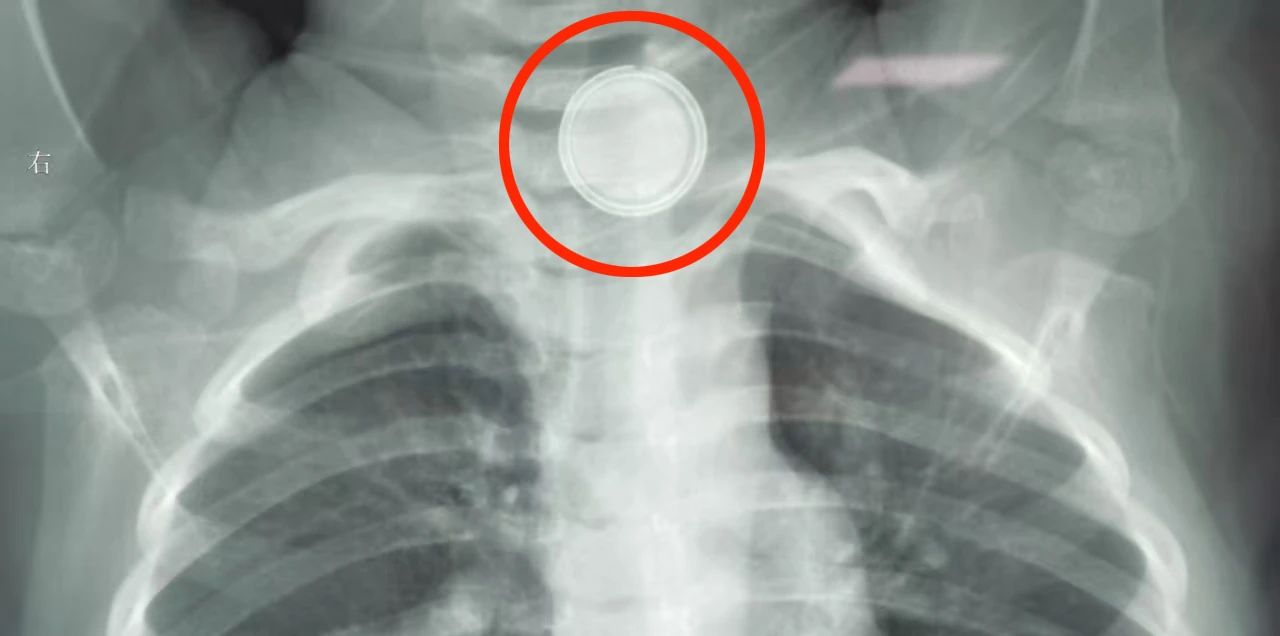

于是,家长立即带其再次就医,经胸片检查发现——食道第一狭窄处,即胸骨上方,竟卡着一块纽扣电池!考虑到当地医疗条件有限,家长不敢耽搁,马不停蹄地带小敏赶往北京儿童医院集团医院·长春市儿童医院。

由于电流腐蚀,电池周围的食道黏膜已经糜烂,布满黑色附着物,并伴有充血肿胀。为了让创面尽快恢复,耳鼻喉科医护人员又为患儿进行了下鼻饲处理。经过一段时间的精心治疗,患儿已经治愈出院。

需要注意的是,虽然误吞纽扣电池取出手术本身不复杂,但其背后却隐藏着巨大风险。电池在食道内会持续放电,就像一颗“定时炸弹”,不断腐蚀食道周围黏膜,造成烧灼伤。进入瘢痕期后,很可能出现食道狭窄,必要时需要进行球囊扩张。更可怕的是,如果电池卡在食道第二狭窄处。由于此处邻近心脏,主动脉弓也在附近,烧灼伤一旦渗透到肌层,食道和气管之间可能形成瘘道,极少数情况下甚至会引发大出血,危及生命。